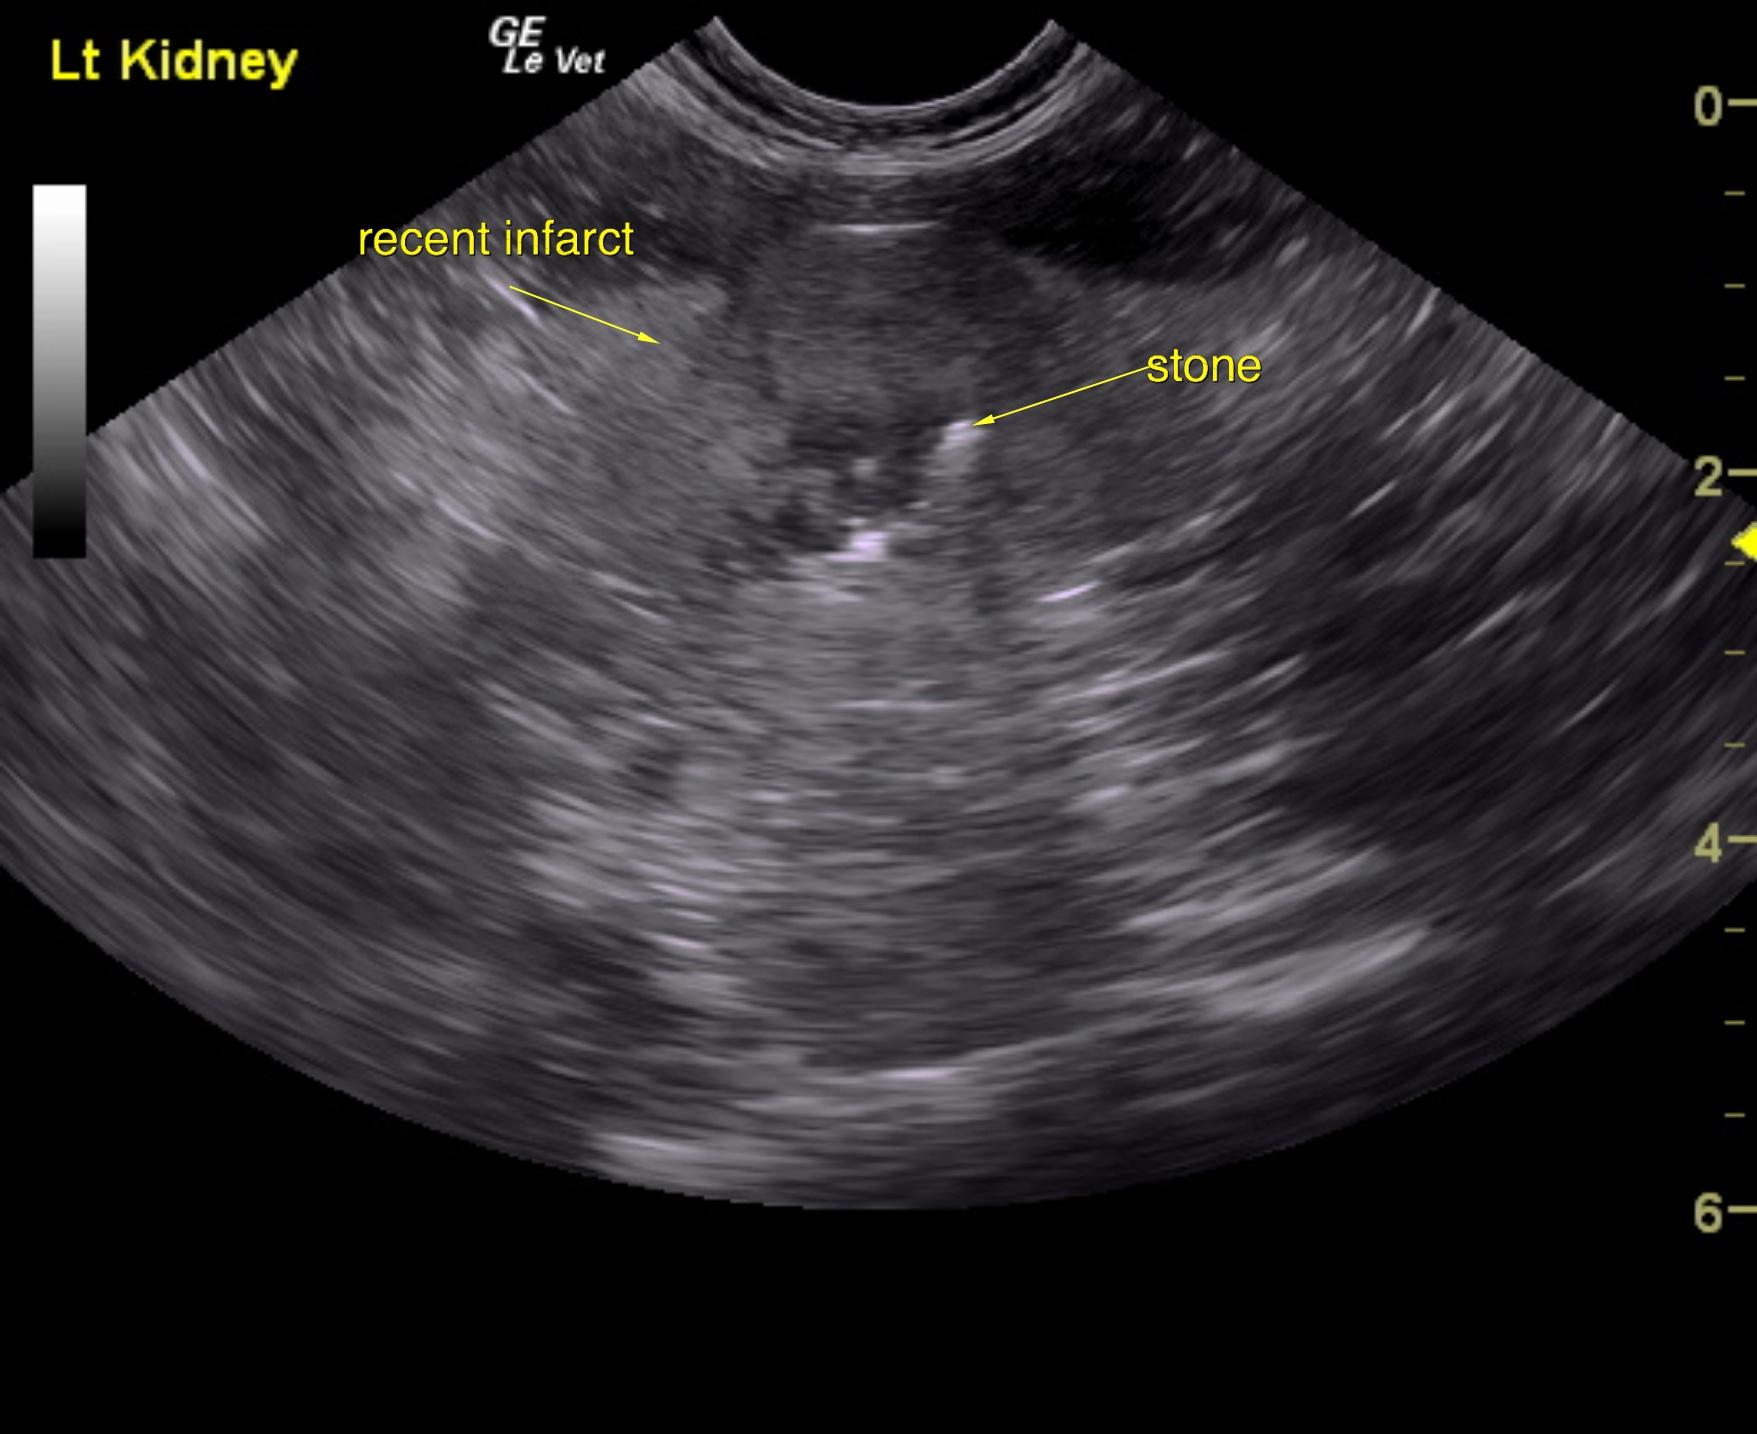

A 5-year-old NM DSH was presented for evaluation of weight loss and a 5-day history of decreased appetite and lethargy. On physical examination 8% dehydration, pale mucosa, and a full but easily expressible bladder were present. Abnormalities on CBC and serum biochemistry were mild lymphopenia and neutrophilia, azotemia (BUN >180, creatinine >20), and hypoproteinemia. Survey radiographs showed irregular kidneys with opacities and possible opacities within the urethra.